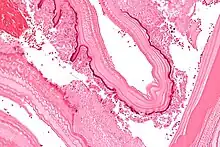

In the human manifestation of the disease, E. granulosus, E. multilocularis, E. oligarthrus and E. vogeli are localized in the liver (in 75% of cases), the lungs (in 5–15% of cases) and other organs in the body such as the spleen, brain, heart, and kidneys (in 10–20% of cases). In people who are infected with E. granulosus and therefore have cystic echinococcosis, the disease develops as a slow-growing mass in the body. These slow-growing masses, often called cysts, are also found in people that are infected with alveolar and polycystic echinococcosis.[9][10]

The cysts found in those with cystic echinococcosis are usually filled with a clear fluid called hydatid fluid, are spherical, and typically consist of one compartment and are usually only found in one area of the body. While the cysts found in those with alveolar and polycystic echinococcosis are similar to those found in those with cystic echinococcosis, the alveolar and polycystic echinococcosis cysts usually have multiple compartments and have infiltrative as opposed to expansive growth.[11][12]

Larval/hydatid cyst stage

From the embryo released from an egg develops a hydatid cyst, which grows to about 5–10 cm within the first year and is able to survive within organs for years.[25] Cysts sometimes grow to be so large that by the end of several years or even decades, they can contain several liters of fluid. Once a cyst has reached a diameter of 1 cm, its wall differentiates into a thick outer, non-cellular membrane, which covers the thin germinal epithelium. From this epithelium, cells begin to grow within the cyst. These cells then become vacuolated, and are known as brood capsules, which are the parts of the parasite from which protoscolices bud. Often, daughter cysts also form within cysts.[24]